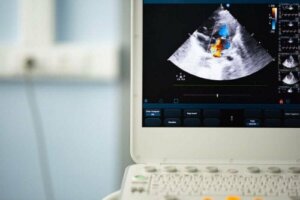

Met een stethoscoop naar je hartgeluiden luisteren en een echocardiogram zijn twee effectieve technieken om deze aandoening te diagnosticeren. De diagnose voor een bicuspide aortaklep begint door je familiegeschiedenis te bekijken.

Tijdens de controle kunnen ze een stethoscoop gebruiken om de onregelmatige hartkloppingen te kunnen horen en ook voor tekenen van een hartruis. Om te controleren of je een bicuspide aortaklep hebt, zullen ze daarna een echocardiogram maken om te evalueren hoe het hart werkt.